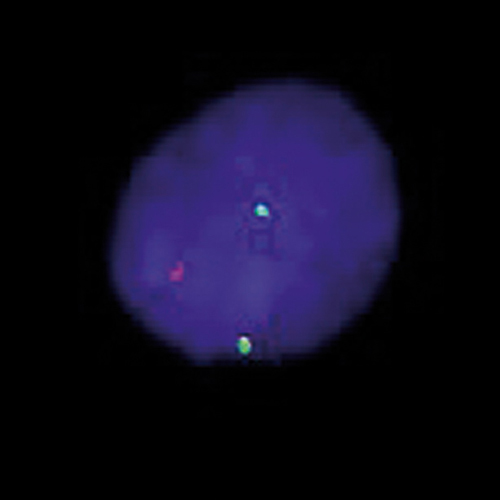

MYCN (2p24) / AFF3 (2q11) hybridized to a cell line showing amplification of MYCN on chromosome 13 and 15. Image kindly provided by Pasteur Workshop 2008, Paris.

Amplification of the human protooncogene, v-myc avian myelocytomatosis viral oncogene neuroblastoma derived homolog (MYCN) is frequently seen either in extrachromosomal double minutes or in homogeneously staining regions of aggressively growing neuroblastomas. MYCN amplification has been defined by the INRG as > 4-fold MYCN signals compared to 2q reference probe signals. The MYCN (2p24) FISH probe is optimized to detect copy numbers of the MYCN gene region at 2p24. The AFF3 gene region probe at 2q11 is included to facilitate chromosome identification.